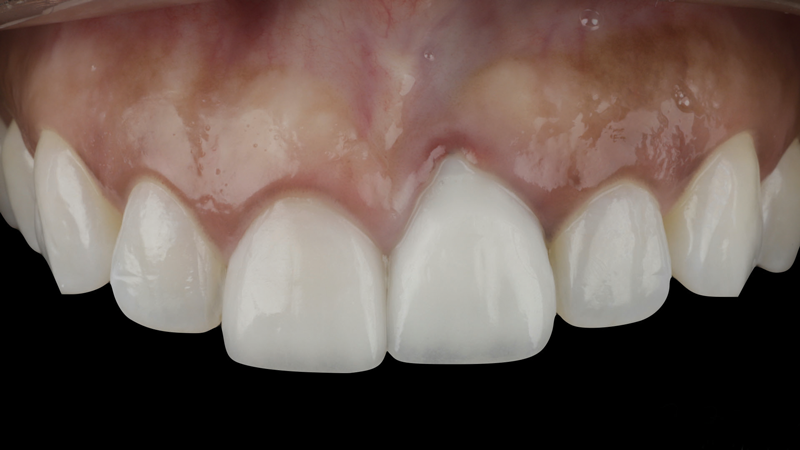

(19.) Four-month postoperative frontal and occlusal views revealing an ideal position of the tooth No. 9 margin in relation to its contralateral counterpart and an abundant amount of supracrestal soft tissue.

Figure 19

(20.) Four-month postoperative frontal and occlusal views revealing an ideal position of the tooth No. 9 margin in relation to its contralateral counterpart and an abundant amount of supracrestal soft tissue.

Figure 20

A patient presented for the restoration of an implant that had been placed at the site of tooth No. 9, which exhibited a residual soft-tissue deficiency and an undulating facial soft-tissue morphology (Figure 11). The objective of the treatment was to change the appearance and thickness of the facial soft tissue prior to crown placement to optimize the esthetics and prevent future soft-tissue dehiscence. After flap reflection (Figure 12), a graft was acquired from the patient's tuberosity to augment the supracrestal soft tissue (Figure 13). A volume-stable collagen matrix was then placed to further increase the thickness of the soft tissue adjacent to the implant body (Figure 14), and the flap was sutured closed (Figure 15). Following a 3-month healing period, a positive change in the soft tissue's morphology was apparent; however, its volume remained deficient when compared with that of tooth No. 8 (Figure 16). When the screw-retained crown was delivered, a second graft was acquired from the tuberosity and placed to further increase the volume of the supracrestal soft tissue (Figure 17 and Figure 18). A postoperative healing period of 4 months resulted in an ideal position of the margin of tooth No. 9 with regard to its contralateral counterpart as well as more natural looking soft-tissue morphology and excellent supracrestal soft-tissue thickness (Figure 19 and Figure 20). Eight months postoperatively, the position of the gingival margin and the thickness of the soft tissue had been maintained (Figure 21 and Figure 22).